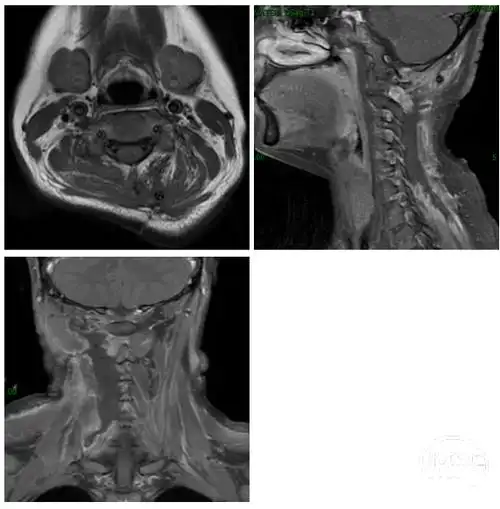

颈部韧带样纤维瘤病影像诊断

中国医学科学院肿瘤医院万经海教授头颈部韧带样纤维瘤一例